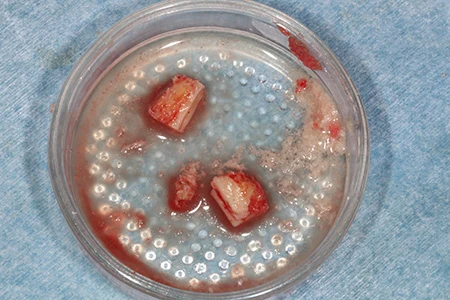

下顎の奥(親知らずが生える部分の横あたり)からブロックの塊の骨を採取し、チタンスクリューで骨に固定します。

固定した骨の周りにウシ由来の人工骨を移植します。